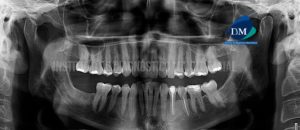

224 – Osteoma en seno maxilar

Se realiza una interconsulta para evaluación tomográfica de un paciente femenino de 36 años, por hallazgo de una “masa ósea” dentro del seno maxilar. En